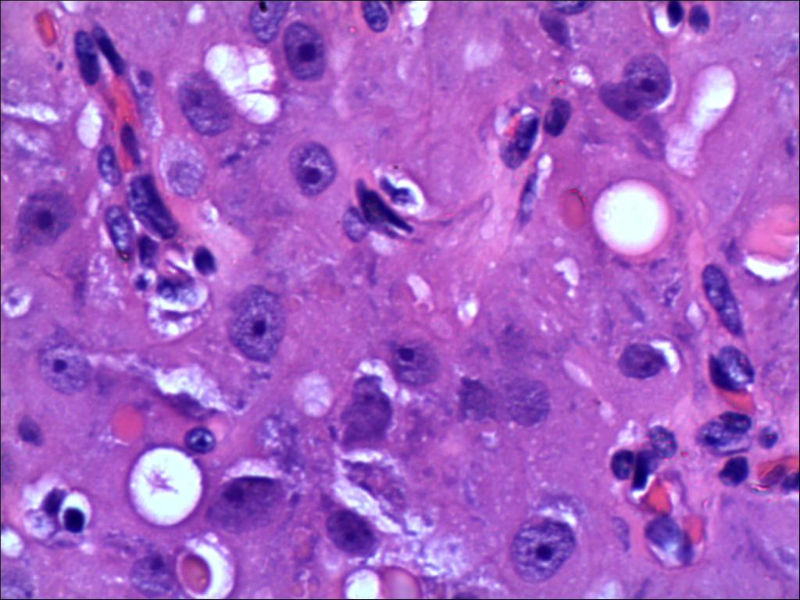

女,27岁,送检右侧卵巢肿物(另外还送检左侧卵巢肿物,大体及镜下显示为畸胎瘤),卵圆形,大小2×1×1cm,似有包膜。卵巢肿物图1

不好意思,可能是我没说清楚,患者对侧卵巢是畸胎瘤,不是同一侧的,我初步考虑门细胞瘤,图21,22,24,25,26中央的一些细胞是不是很像门细胞

其中一些大细胞怎么解释,建议在传一些中倍的图,图片有些暗了。

谢谢大家的回答和解疑,忘记一个重要的病史,就是该女性为产妇。但是妊娠黄体瘤与类固醇细胞瘤怎么鉴别呢

那应该是妊娠黄体/黄体瘤,类固醇细胞瘤有嗜酸细胞和组织细胞样细胞两种,此例显然不是。